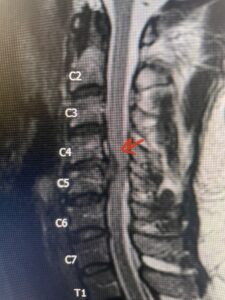

This 47-year-old male who four months prior was lifting weights developed sharp pain in his neck. After that he developed progressive numbness in his arms, neck pain and headache. He said that the right arm was worse than the left. On examination the patient had long tract weakness on the right side which included his triceps, finger extensors, hip flexors, and dorsiflexors. The patient did not have hyperreflexia. MRI (Fig. 2) demonstrated a massive, extruded disc herniation with severe cord compression. The patient because of progressive myelopathy and spinal cord compression was indicated for anterior cervical discectomy and fusion at C4-5 (Fig. 3). Patient had significant improvement of weakness and numbness post operatively.

Fig. 2a Sagittal T2-weighted cervical MRI demonstrating large C4-5 herniated disc with spinal cord compression (red arrow)